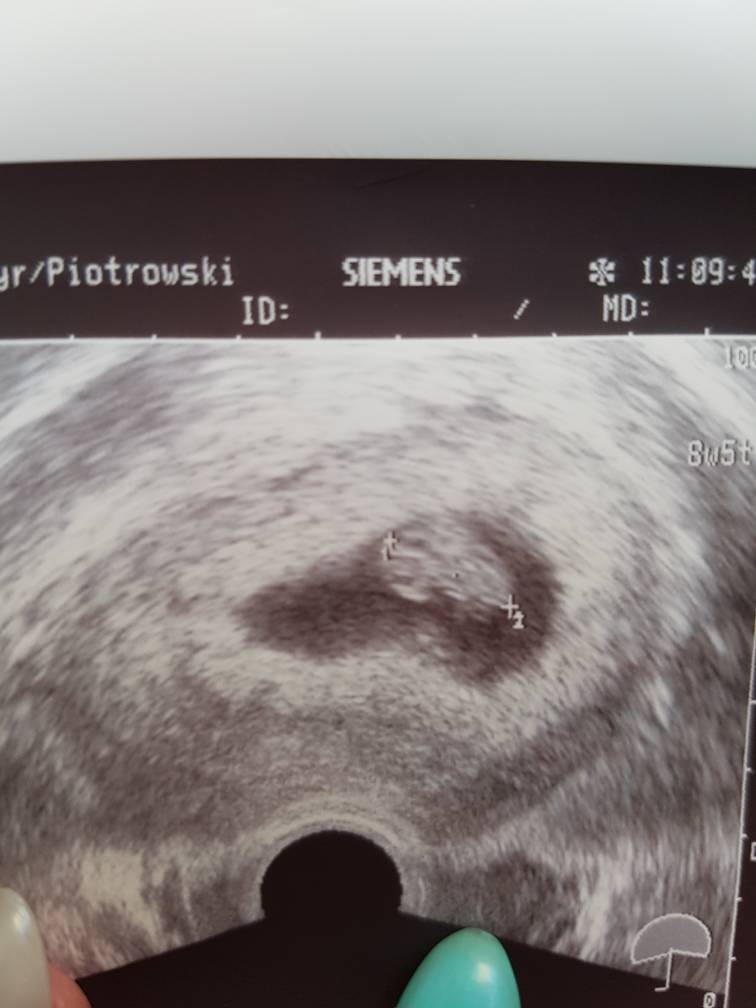

1493370399-aaaaaa.jpeg

cale 1,9 cm mojego szczescia :) wszystko super. Nastepna wizyta za 4 tygodnie ;)